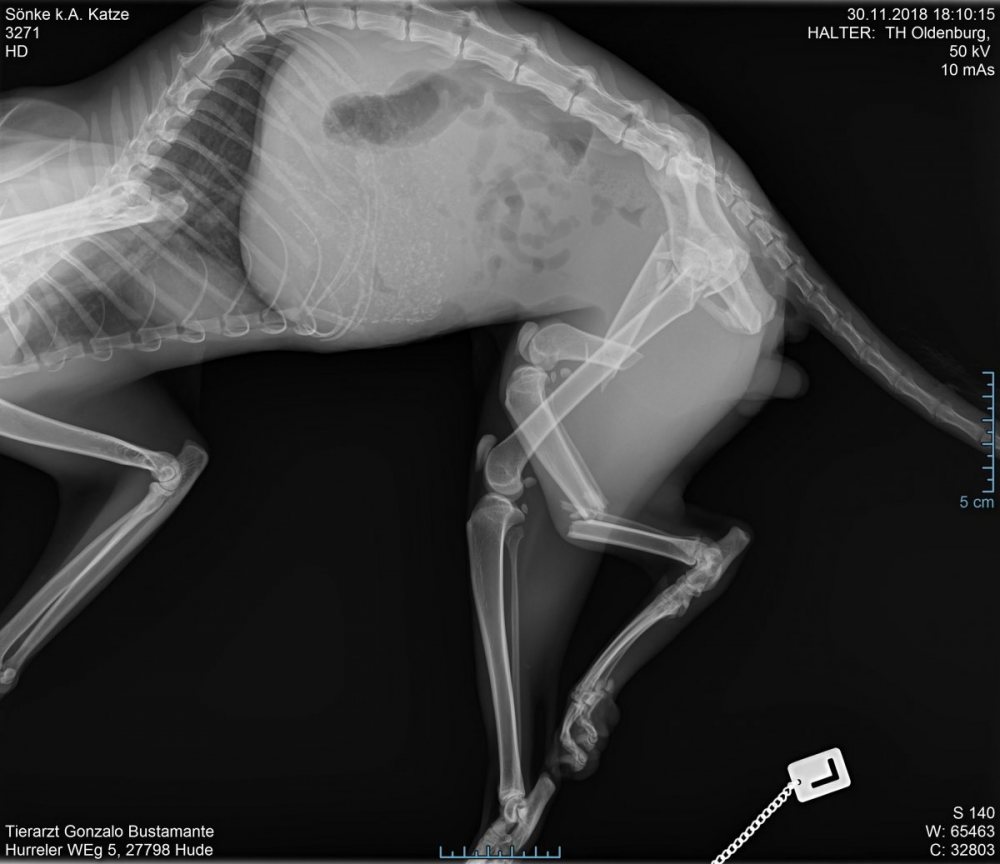

In der Praxis legte man mich sofort in Narkose und beim Einschlafen hörte ich noch, wie die Tierärztin sagte, dass man mein Bein eigentlich gar nicht röntgen bräuchte… es sei komplett zerquetscht und kein Knochen wäre mehr an der richtigen Stelle.